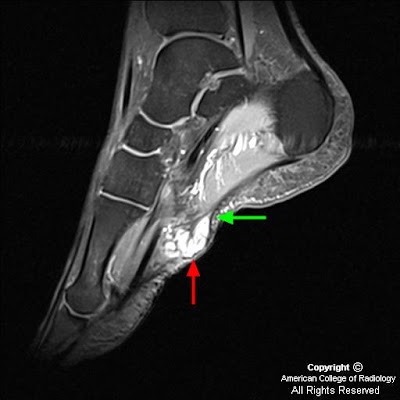

Плантарный фиброматоз (синдром Леддерхозе, описан им в 1897 г) в отличие от пальмарного фиброматоза редко сопровождается сгибательиой контрактурой. Поражает обычно медиальный отдел подошвы стопы (плантарный апоневроз) и имеет вид узелков, с течением времени достигающих 4—5 см в поперечнике. Узлы обычно плотные, множественные, связаны с фасциальными образованиями. Микроскопически новообразованная ткань богата фибробластоподобиыми клетками.

Подошвенный фиброматоз

Плантарный фиброматоз